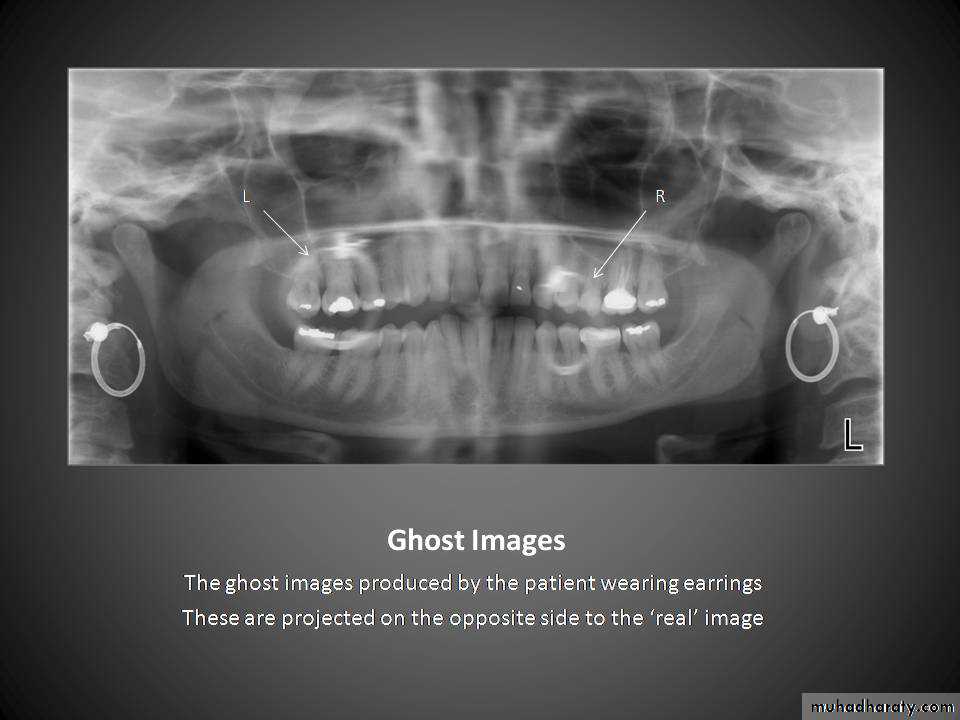

What kind of crowns?What is this?!?